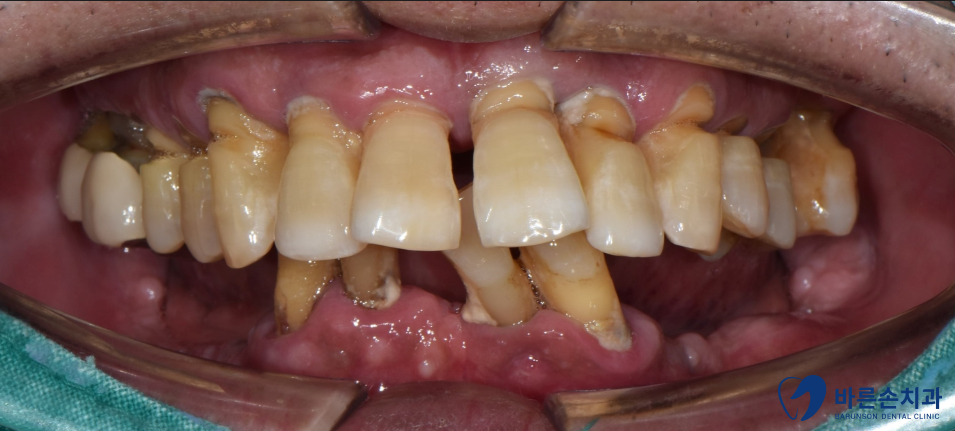

초진 사진

치아를 보시면 주변에 치태, 치석이 방치가 되어있습니다.

잇몸도 빨갛게 부어있고 치아도 옆으로 쓰러져있네요.

당연히 식사 시 매우 불편하십니다 ㅠㅠ